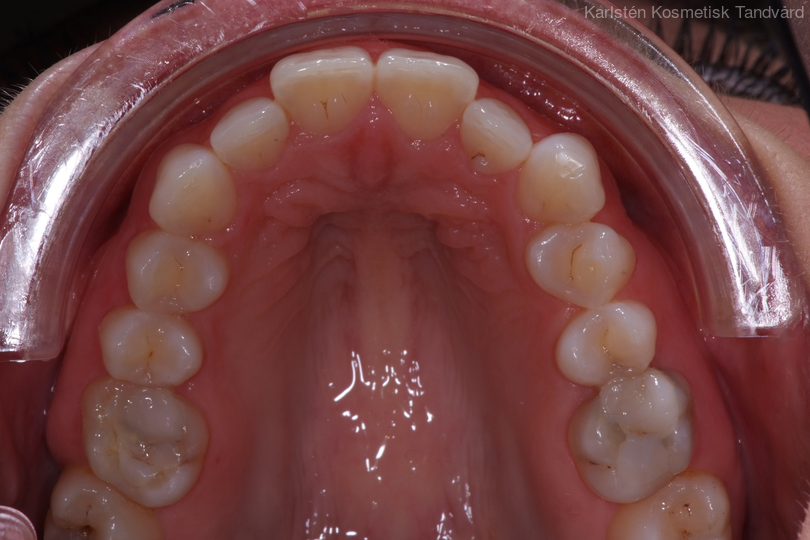

1 Ojämn tandrad

- Trångställda tänder 1